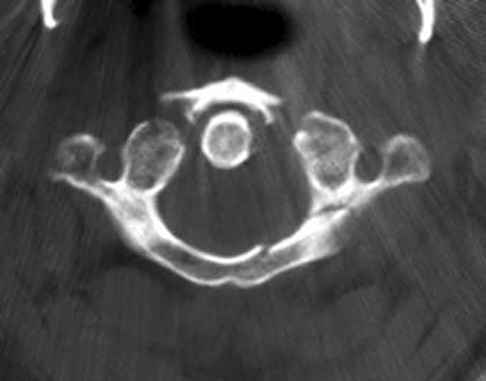

CLINICAL SITUATION

Figure 1 shows a CT from the cervical spine of an 85-year-old woman who fell from a standing height 1 week earlier. She is independent and ambulatory and resides in an assisted living facility. She reports persistent neck pain but denies arm pain or weakness. She is neurologically intact.

Fractures in this region of C2 have a high risk of

1. spinal cord injury.

2. union.

3. nonunion.

4. stroke

Discussion: C

Increased displacement and angulation of odontoid fractures have an increased risk of nonunion. Surgical stabilization has reduced the risks of mortality without increasing the risk of complications compared with nonsurgical treatment options. When treating odontoid fractures, halo vest

immobilization has been shown to increase the risk of dysphagia in the elderly.

Question 7 of 100

The preferred mode of treatment for this patient’s fracture is

1. a halo vest.

2. a hard cervical collar.

3. physical therapy.

4. posterior C1-2 arthrodesisDiscussion: D

Increased displacement and angulation of odontoid fractures have an increased risk of nonunion. Surgical stabilization has reduced the risks of mortality without increasing the risk of complications compared with nonsurgical treatment options. When treating odontoid fractures, halo vest immobilization has been shown to increase the risk of dysphagia in the elderly.

Question 8 of 100

What are the risks associated with halo vest treatment, compared with hard-collar treatment?

1. Increased mobility

2. Dysphagia

3. Spinal cord injury

4. Dysphonia Discussion: B

Increased displacement and angulation of odontoid fractures have an increased risk of nonunion. Surgical stabilization has reduced the risks of mortality without increasing the risk of complications compared with nonsurgical treatment